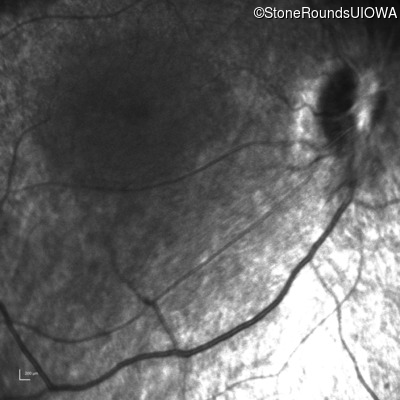

Infrared Fundus Photograph - Left - No Light Perception

Exemplar